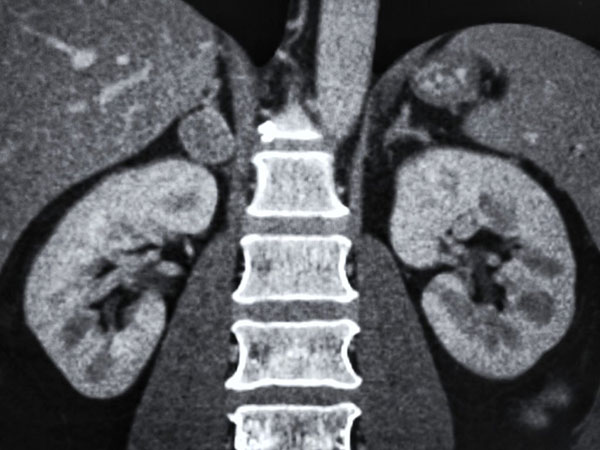

- بیماری کلیه پلی کیستیک که یک اختلال ژنتیکی بوده و موجب تشکیل کیسههای پُر از مایعی در کلیهها شده و معمولا فشار خون را بالا میبرد.

اختلالات ژنتیکی

بیماری کلیه پلی کیستیک، اختلالی است که در آن کیستهایی پُر از مایعات در کلیهها به وجود میآیند. این کیستها میتوانند فشار خون را بالا برده و فرد را در معرض آنوریسم مغزی قرار دهند. آنوریسمها در اشخاصی که بیماری کلیه پلی کیستیک دارند، کمی زودتر خودش را نشان میدهد و نستب به آنوریسمهای معمولی که در افراد دیگر پیدا میشود، کمی بیشتر خونریزی میکند. سندرم اهلرزدانلوس و سندرم مارفان، دو اختلال بافت همبند هستند که در آنها، لایهی میانی شریانها به خوبی شکل نگرفته است؛ بنابراین این افراد دارای شریانهایی با دیوارههایی ضعیف هستند. کسانی که این ناهنجاریها را دارند، دچار انواع آنوریسمها هستند که فقط محدود به مغزشان نمیشود، بلکه در شکم و سینهشان نیز وجود دارد.